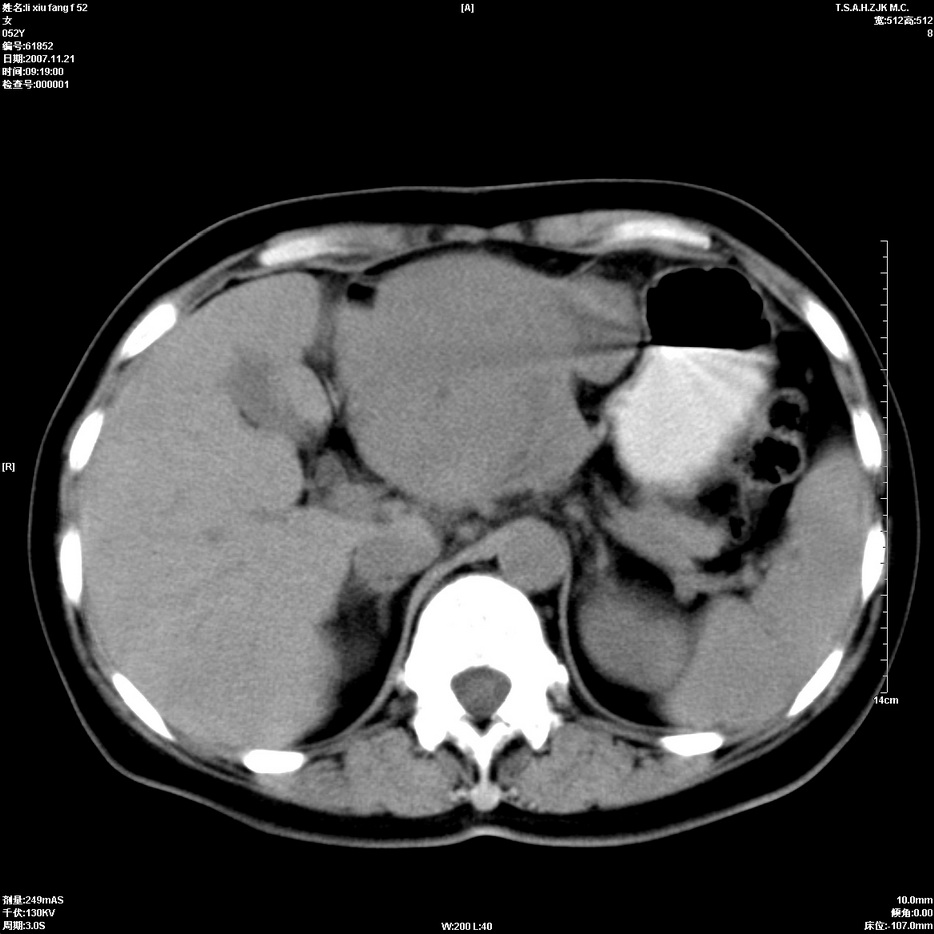

标题: CT12858:女,52岁,胎甲球蛋白861肝左叶占位,肝癌。下腔静 [打印本页]

标题: CT12858:女,52岁,胎甲球蛋白861肝左叶占位,肝癌。下腔静

肝左叶巨大低密度灶肿块,增强符合快进快出表现,有动静脉交通支;静脉期,下腔静脉内有充盈缺损,afp明显升高,支持肝癌并下腔静脉癌栓形成。

以下是引用拾荒者在2008-4-15 22:57:00的发言:[br]肝左叶巨大低密度灶肿块,增强符合快进快出表现,有动静脉交通支;静脉期,下腔静脉内有充盈缺损,afp明显升高,支持肝癌并下腔静脉癌栓形成。